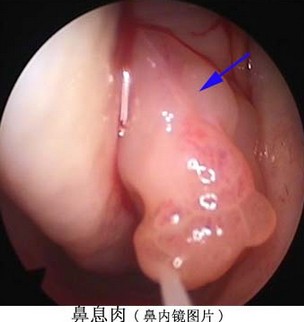

3、鼻內(nèi)窺鏡下“動力回旋術(shù)”: 一清二除三復(fù)查專業(yè)治療鼻息肉效果好

鼻息肉常伴有持續(xù)性鼻塞、嗅覺減退、鼻涕增多、頭痛頭昏等癥狀。且術(shù)后復(fù)發(fā)一直是困擾鼻息肉患者的主要問題。仁品耳鼻喉醫(yī)院鼻病醫(yī)保匯集了全國知名的鼻病醫(yī)生,在治療鼻息肉方面形成了一套完整規(guī)范的治療標(biāo)準(zhǔn):一清二除三復(fù)查,治療效果好。